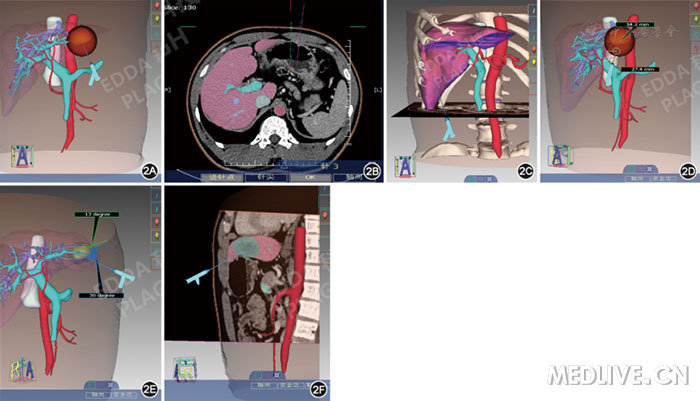

http://webres.medlive.cn/upload/000/307/107

图2  IQQA技术平台对腹腔镜下消融治疗肝癌行手术规划图像:2A示根据肿瘤大小选择合适的消融针;2B示设计进针点和针尖位置;2C示标记进针点的体表标记;2D示针道进入体表、肝脏的距离演算;2E示针道与轴面、矢状面的角度演算;2F示经过针道模拟腹腔镜超声的图像